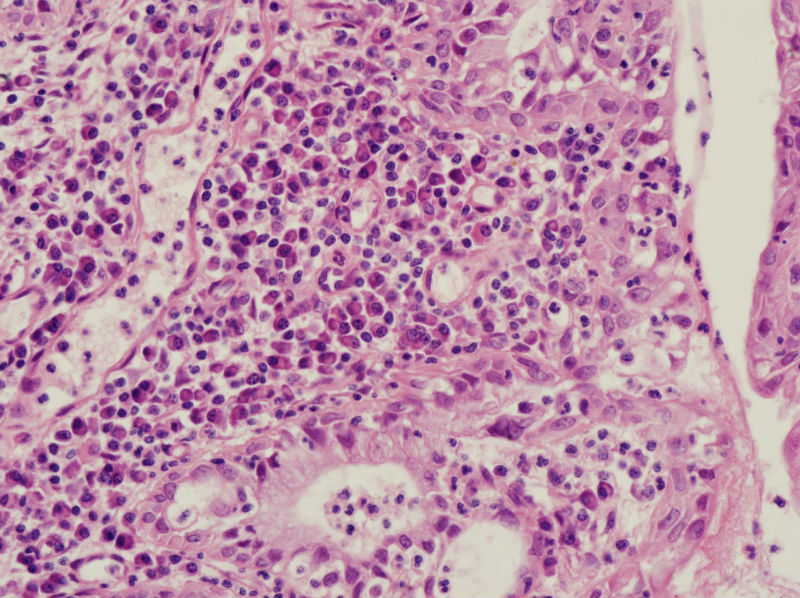

45岁,宫颈息肉?请老师指教

图4

我想请问,息肉的分型.另外患者服用大量妇科中成药物和腺体的鳞化有关吗?